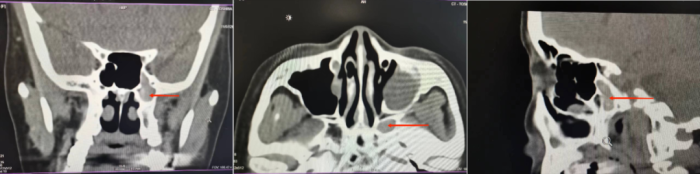

入院后耳鼻喉科主任龚正鹏结合患者副鼻窦CT发现患者较常人有少见的解剖变异,有少量磨砂样斑片状高密度钙化影,判断患者不仅仅是单纯慢性鼻窦炎,还可能合并有真菌性鼻窦炎,且患者头痛等症状可能与左侧蝶窦旁气房真菌感染有关。

与患者充分沟通后,龚正鹏主刀为患者行手术治疗。术中仔细用探针探查蝶窦旁气房,发现大量干酪样豆腐渣样物引流,证实为真菌感染,术后患者疼痛等症状完全缓解,康复出院。